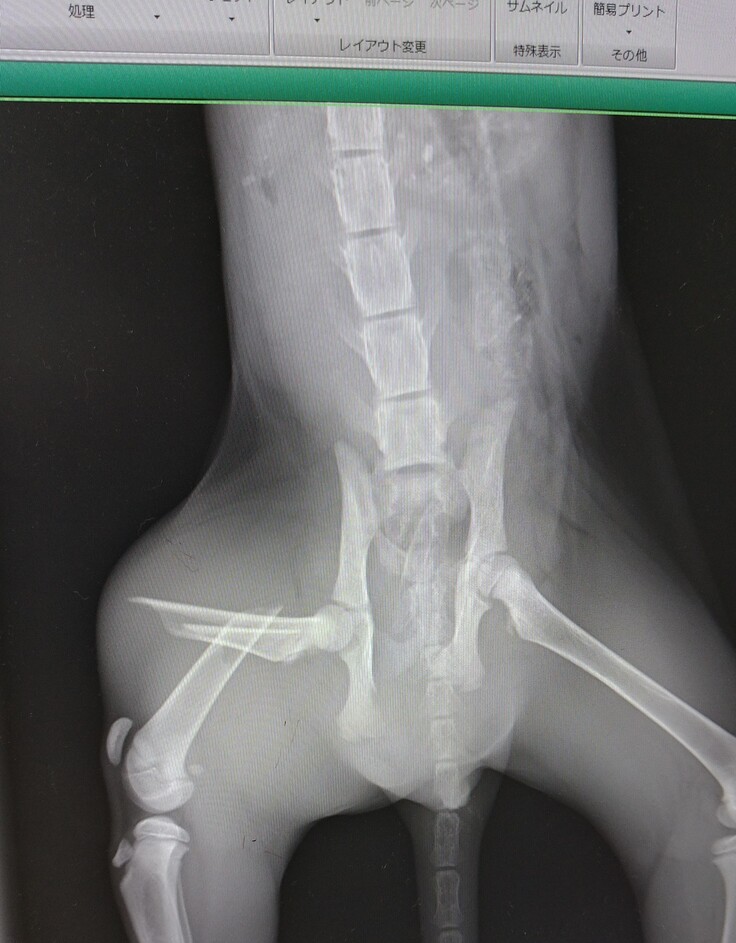

いつもお世話になっている動物病院に連れていき、診察していただいた結果は「骨盤と大腿骨の骨折」。

性別はオスで、生後4ヶ月ぐらいだそうです。

現在は骨折の手術を終え、順調に回復しています。